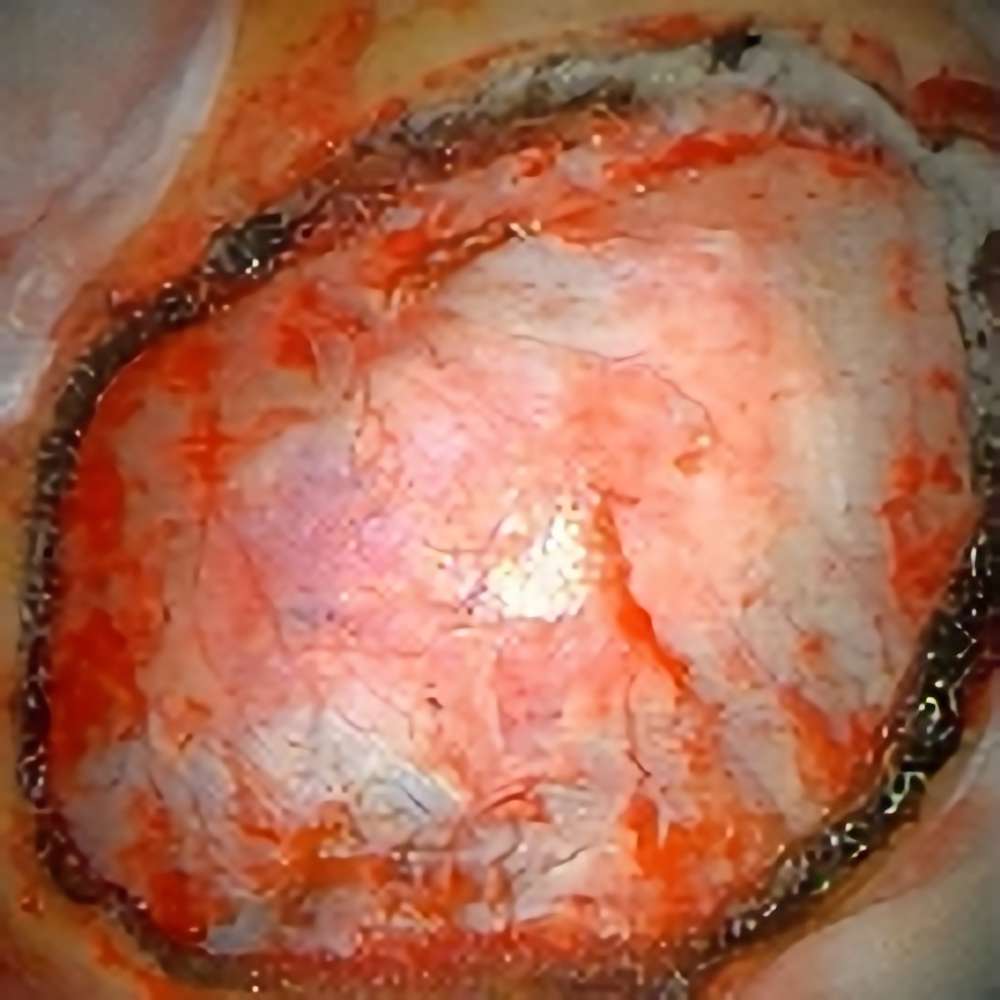

No.’22_89 摘出 前

No.’22_89  摘出 中

No.’22_89 摘出 後